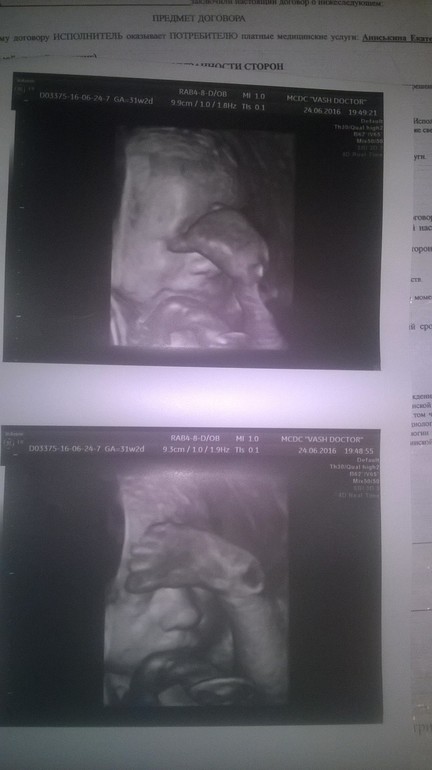

Это малыш в 30 недель и 2 дня

Наша фотосессия на 32 недели )

Все фото супер! Но второе просто отпад!!! Я и не знала что они ногой до лица достают))